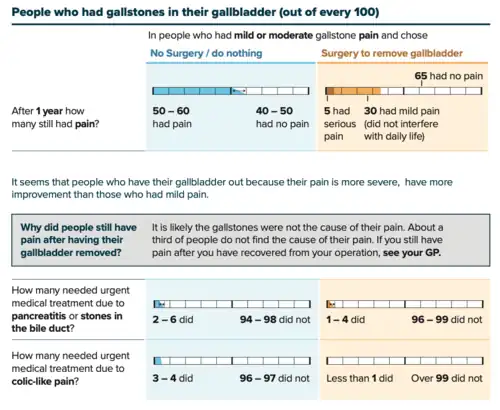

Surgical

Cholecystectomy (gallbladder removal) has a 99% chance of eliminating the recurrence of cholelithiasis. The lack of a gallbladder has no negative consequences in most people, however 10 to 15% of people develop postcholecystectomy syndrome,[48] which may cause nausea, indigestion, diarrhea, and episodes of abdominal pain.[49]

There are two surgical options for cholecystectomy:

- Open cholecystectomy is performed via an abdominal incision (laparotomy) below the lower right ribs. Recovery typically requires 3–5 days of hospitalization, with a return to normal diet a week after release and to normal activity several weeks after release.[54]

- Laparoscopic cholecystectomy, introduced in the 1980s, is performed via three to four small puncture holes for a camera and instruments. Post-operative care typically includes a same-day release or a one-night hospital stay, followed by a few days of home rest and pain medication.[54] Perforation of the gall bladder is not uncommon—it has been reported in the range of 10% to 40%. Unretrieved gallstone spillage has been reported as 6% to 30%, but gallstones that are not retrieved rarely cause complications (0.08%–0.3%).[55]

Obstruction of the common bile duct with gallstones can sometimes be relieved by endoscopic retrograde sphincterotomy (ERS) following endoscopic retrograde cholangiopancreatography (ERCP).[58]

Surgery carries risks and some people continue to experience symptoms (including pain) afterwards, for reasons that remain unclear. An alternative option is to adopt a ‘watch and wait’ strategy before operating to see if symptoms resolve. A study compared the 2 approaches for uncomplicated gallstones and after 18 months, both approaches were associated with similar levels of pain. The watch and wait approach was also less costly (more than £1000 less per patient).[60][61]